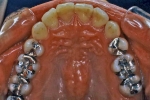

治療中

|